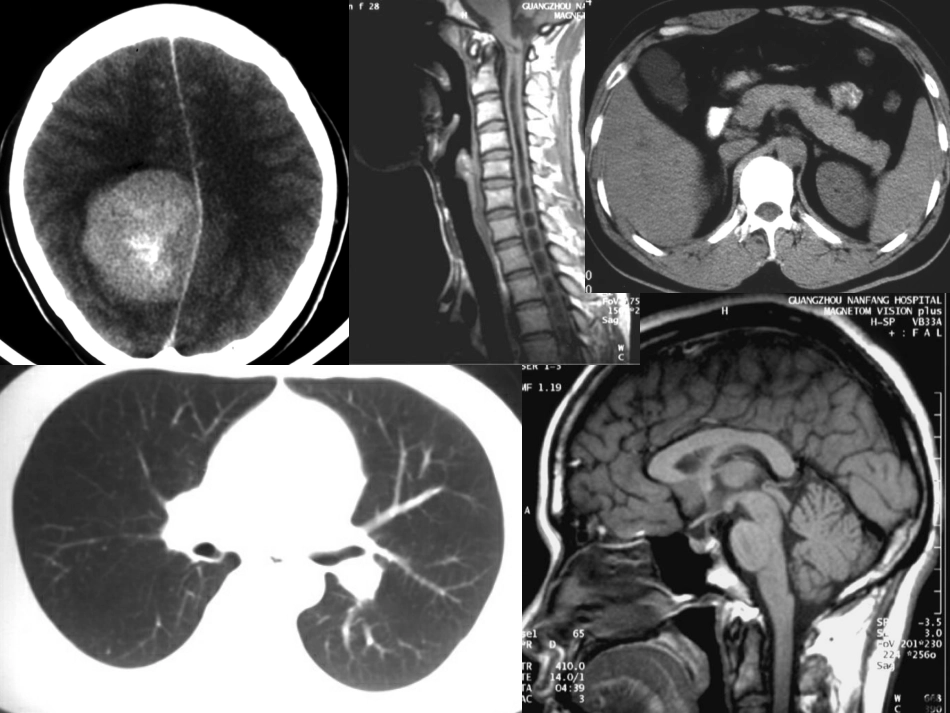

CT诊断学第一军医大学南方医院影像中心陈燕萍第一节总论一:发展概况二:CT成像原理三:CT机的基本结构四:CT图像特点五:CT检查方法六:CT图像分析什么是CT?CT是通过X线管环绕人体某一层面进行扫描,测得该层面中各点吸收X线的数据,然后利用计算机高速运算和图像重建原理,获得该层面图像。CT机的基本结构一、扫描装置(扫描机架和检查床)X线管,探测器,信号转换系统,准直仪X线扫描数据的收集和转换二、计算机系统扫描数据处理和重建图像三、图像显示与记录图像显示及存贮CT检查的特点•图像清晰,密度分辨率高•CT图像是真正的断面图像,无前后重叠•CT检查无创伤,无痛苦,CT图像特点CT图像.CT图像是由不同灰度的小方块(像素)按矩阵排列构成.图像质量与象素大小有关像素越小,数目越多,图像越细致.CT图像在荧屏上有由黑到白的不同灰度黑表示低吸收区-----低密度(脑室)白表示高吸收区——高密度(颅骨)CT图像特点CT值.CT值即代表CT图像象素内组织结构线性衰减系数相对值的数值Um-Uw.公式:某物质CT值=———X1000Uw.单位:Hu.骨软组织水脂肪空气★CT图像特点窗宽与窗位.窗宽是指荧屏图像上包括16个灰阶的CT值范围.窗位是指观察某一组织结构细节时,以该组织CT值为中心观察.加大窗宽,图像层次增多,组织对比降低提高窗位,图像变黑降低窗位,图像变白★CT图像特点CT分辨力:.空间分辨力是指CT对于物体空间大小的鉴别能力,常用可辨别最小物体的直径来表示。CT的空间分辨力不如X线照片。.密度分辨力是指CT对密度差别的分辨能力。以百分数表示。CT的密度分辨力较普通X线检查高10-20倍。★CT图像特点伪影:指在被扫描物体中并不存在而图像中却显示出来的各种不同类型的影像。.与病人有关:呼吸心跳,躁动,高密度异物.与机器有关.伪影影响图像质量,在诊断时应注意CT图像特点部分容积效应:在同一扫描层面内含有两种以上不同密度而又相互重叠的物质时,所测CT值不能如实反映其中任何一种物质的CT值,这种现象称为部分容积现象。在诊断中,对小病变CT值的评价要注意:•病变密度高于周围组织而厚度小于层面厚度,则所测病变CT值低于其本身。•病变密度低于周围组织而厚度小于层面厚度,则所测病变CT值要高于其本身。CT检查方法1平扫:PrecontrastScan/Non-ContrastScan指不用对比增强或造影的普通扫描,横/冠状面层厚=层距:连续扫描,层厚>层距:间隔扫描层厚<层距:重叠扫描2增强扫描PostContrastScan/ContrastScan.指经静脉注入水溶性碘造影剂(60%泛影葡胺60~100ml)后再行扫描.常用快速团注法(bolusinjection),以2ml/秒速度快速注入全部对比剂。3造影扫描:器官或结构内注入造影剂后再扫描如:口服胆囊造影CT,脊髓造影CT(CTM)★CT检查方法4特殊扫描:①局部薄层及放大扫描,层厚=1~3mm,缩小FOV,有利于观察微小病变.②重叠扫描,进床距离小于层厚(如层厚8mm,进床距离5mm)③延迟(增强)扫描(DelayScanCT)④动态增强扫描CT的新技术螺旋CT扫描:SpiralCT,HelicalCT螺旋CT是通过滑环技术与扫描床连续平直移动而实现的。在扫描时,X线管连续旋转并进行连续扫描,检查床沿纵轴连续平直移动,这样管球旋转与连续动床同时进行,使X线扫描的轨迹呈螺旋状,因而得名。多排螺旋CT:multidetectorCT普通CT与螺旋CT的比较常规CT:间隔式扫描螺旋CT:连续容积扫描,轨迹呈螺旋形MSCT:一次扫描获得4层图像CT的新技术螺旋CT的优点:1没有扫描间隔时间,大大缩短扫描时间2快速容积扫描,提高小病灶的检出,防止遗漏小病灶3能进行容积扫描后处理:CT血管造影,CT三维重建,CT仿真内窥镜等。CT的新技术CT三维重建图像(ThreeDimensionalReconstructionImaging,3D-CT)多层面重建法(MultiplanarReconstruction,MPR)表面遮盖法(SurfaceShadedDisplay,SSD)MIP与SSD重建技术比较MIP:可分辨血管壁钙化与充盈造影剂的血管腔SSD:不能反映灰阶度CT的新技术•CT血管成像(CTA).是静脉内注入对比剂后行血管造影CT扫描的重建技术,可立体地显示血管影像。.目前主要用于脑血管、肾动脉与肺动脉等,对小血管的显示不够理想。.仿真血管内镜可清楚显示血管腔,用于诊断动脉夹层和肾动脉狭窄...